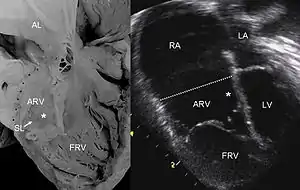

| Pathological specimen and ultrasound image of a heart with Ebstein's anomaly: Abbreviations: RA: right atrium; ARV: atrialized right ventricle; FRV: functional right ventricle; AL: anterior leaflet; SL: septal leaflet; LA: left atrium; LV: left ventricle; asterisk: grade II tethering of the tricuspid septal leaflet | |